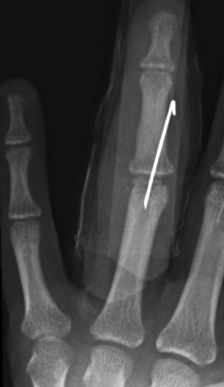

D4. Fracturas intraarticulares (condílea):

Se pueden diferenciar fracturas por avulsión, unicondíleas o intracondíleas, bicondíleas o transcondíleas y osteocondrales. Suelen afectar a la falange proximal y su tratamiento es complejo. Como cualquier fractura intraarticular deben reducirse anatómicamente dejando una articulación congruente para evitar secuelas de rigidez.

Se puede intentar realizar una reducción cerrada de la fractura, pero generalmente termina siendo necesaria la reducción abierta y estabilización con agujas (Figura 25)

Figura 25: a- fractura intra-articular del cóndilo de la falange proximal. Tratamiento quirúrgico mediante reducción abierta y osteosíntesis con aguja de Kirschner. b, c-Imagen radiológica con buena reducción y congruencia articular